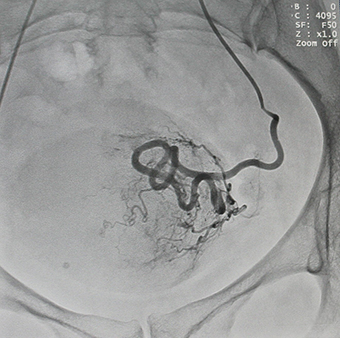

Эмболизация маточных артерий осуществляется рентген-хирургом в операционной,оснащенной ангиографической аппаратурой, под рентген-контролем. Доступом через бедренную или плечевую артерию при помощи специального катетера эмболизирующий препарат доставлен в артерии, питающие миому – последовательно справа и слева. Микроэмболы размером 500-700нм проникают в сосуды узла, блокируя их просвет, но в силу своих физических характеристик практически не попадают в сосуды, кровоснабжающие здоровые ткани. Питание тканей миомы прекращается, миома замещается соединительной тканью, уменьшается в размерах и как правило не требует дальнейшего лечения.

Кровоток в узле до ![]() |

и после процедуры эмболизации![]() |